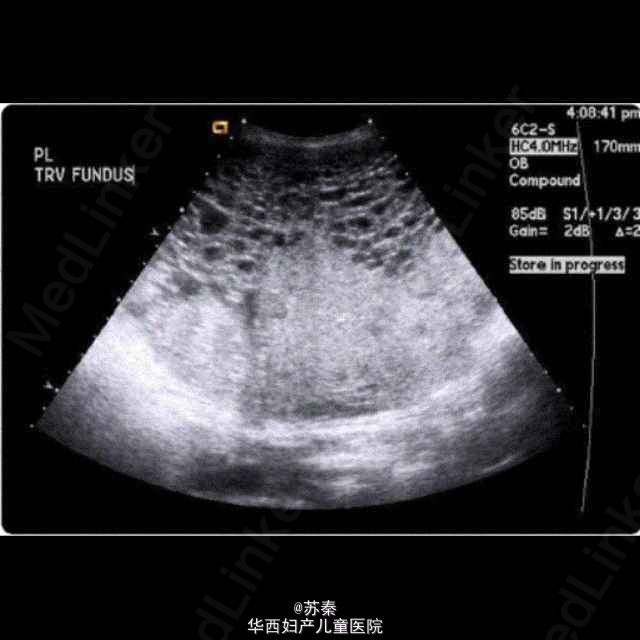

胎盘间叶细胞发育不良一例

苏医师   四川大学华西第二医院

21岁女性,G3P0111。 19周超声示正常胎儿和孕囊,X片,肝肾功能均无异常。 于33周顺产一正常女婴。 胎盘肉眼观,胎盘胎儿面有许多扩张的绒毛膜静脉,切面可见在正常软组织之间有无数扩张的囊性结构,切有一个直径约3cm的绒毛膜血管瘤。 病理切片可见显著扩张的绒毛膜血管和扩张的中央池囊,以及增厚的纤维肌静脉壁,松弛的粘液状基质和绒毛膜血管。